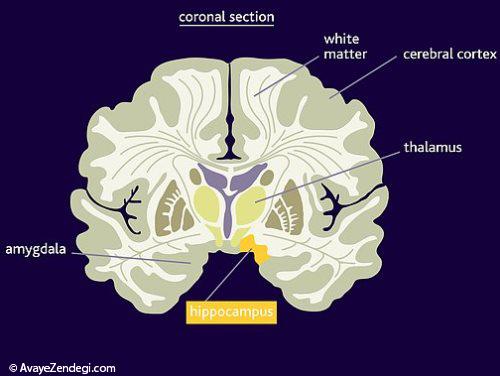

7- با توجه به مطالعات انجام شده، اگر شما به طور منظم ورزش کنید، می توانید مقدار ماده خاکستری واقع در هیپوکامپ را افزایش دهد.

8- اطلاعاتی جالب؛ ماده خاکستری که 40٪ مغز را تشکیل می دهد، تنها پس از مرگ، به رنگ خاکستری در می آید.

10- مقدار ماده سفید در مغز مردان بیشتر است و تصور می شود این ماده، مایع مغزی نخاعی است.

11- 60 درصد از ماده سفید مغز، از میلین ها تشکیل شده که سرعت انتقال پیام الکتریکی را با کمک این ماده سفید، افزایش می دهد.